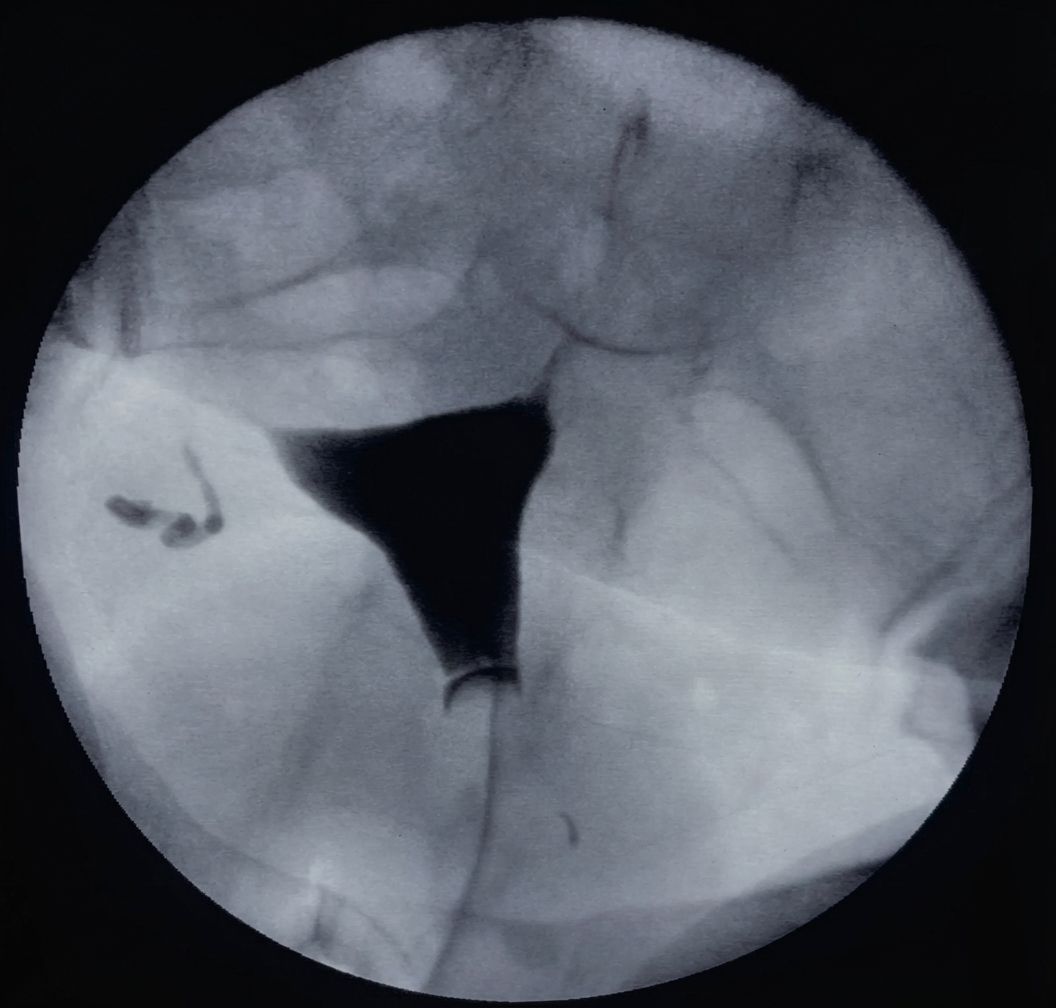

FLUOROSCOPIA

Estudios dinamicos de los sistemas corporales y guia de procedimientos intervencionistas

- Esofagograma

- Cistograma

- Uretrocistografía

- Histerosalpingografia